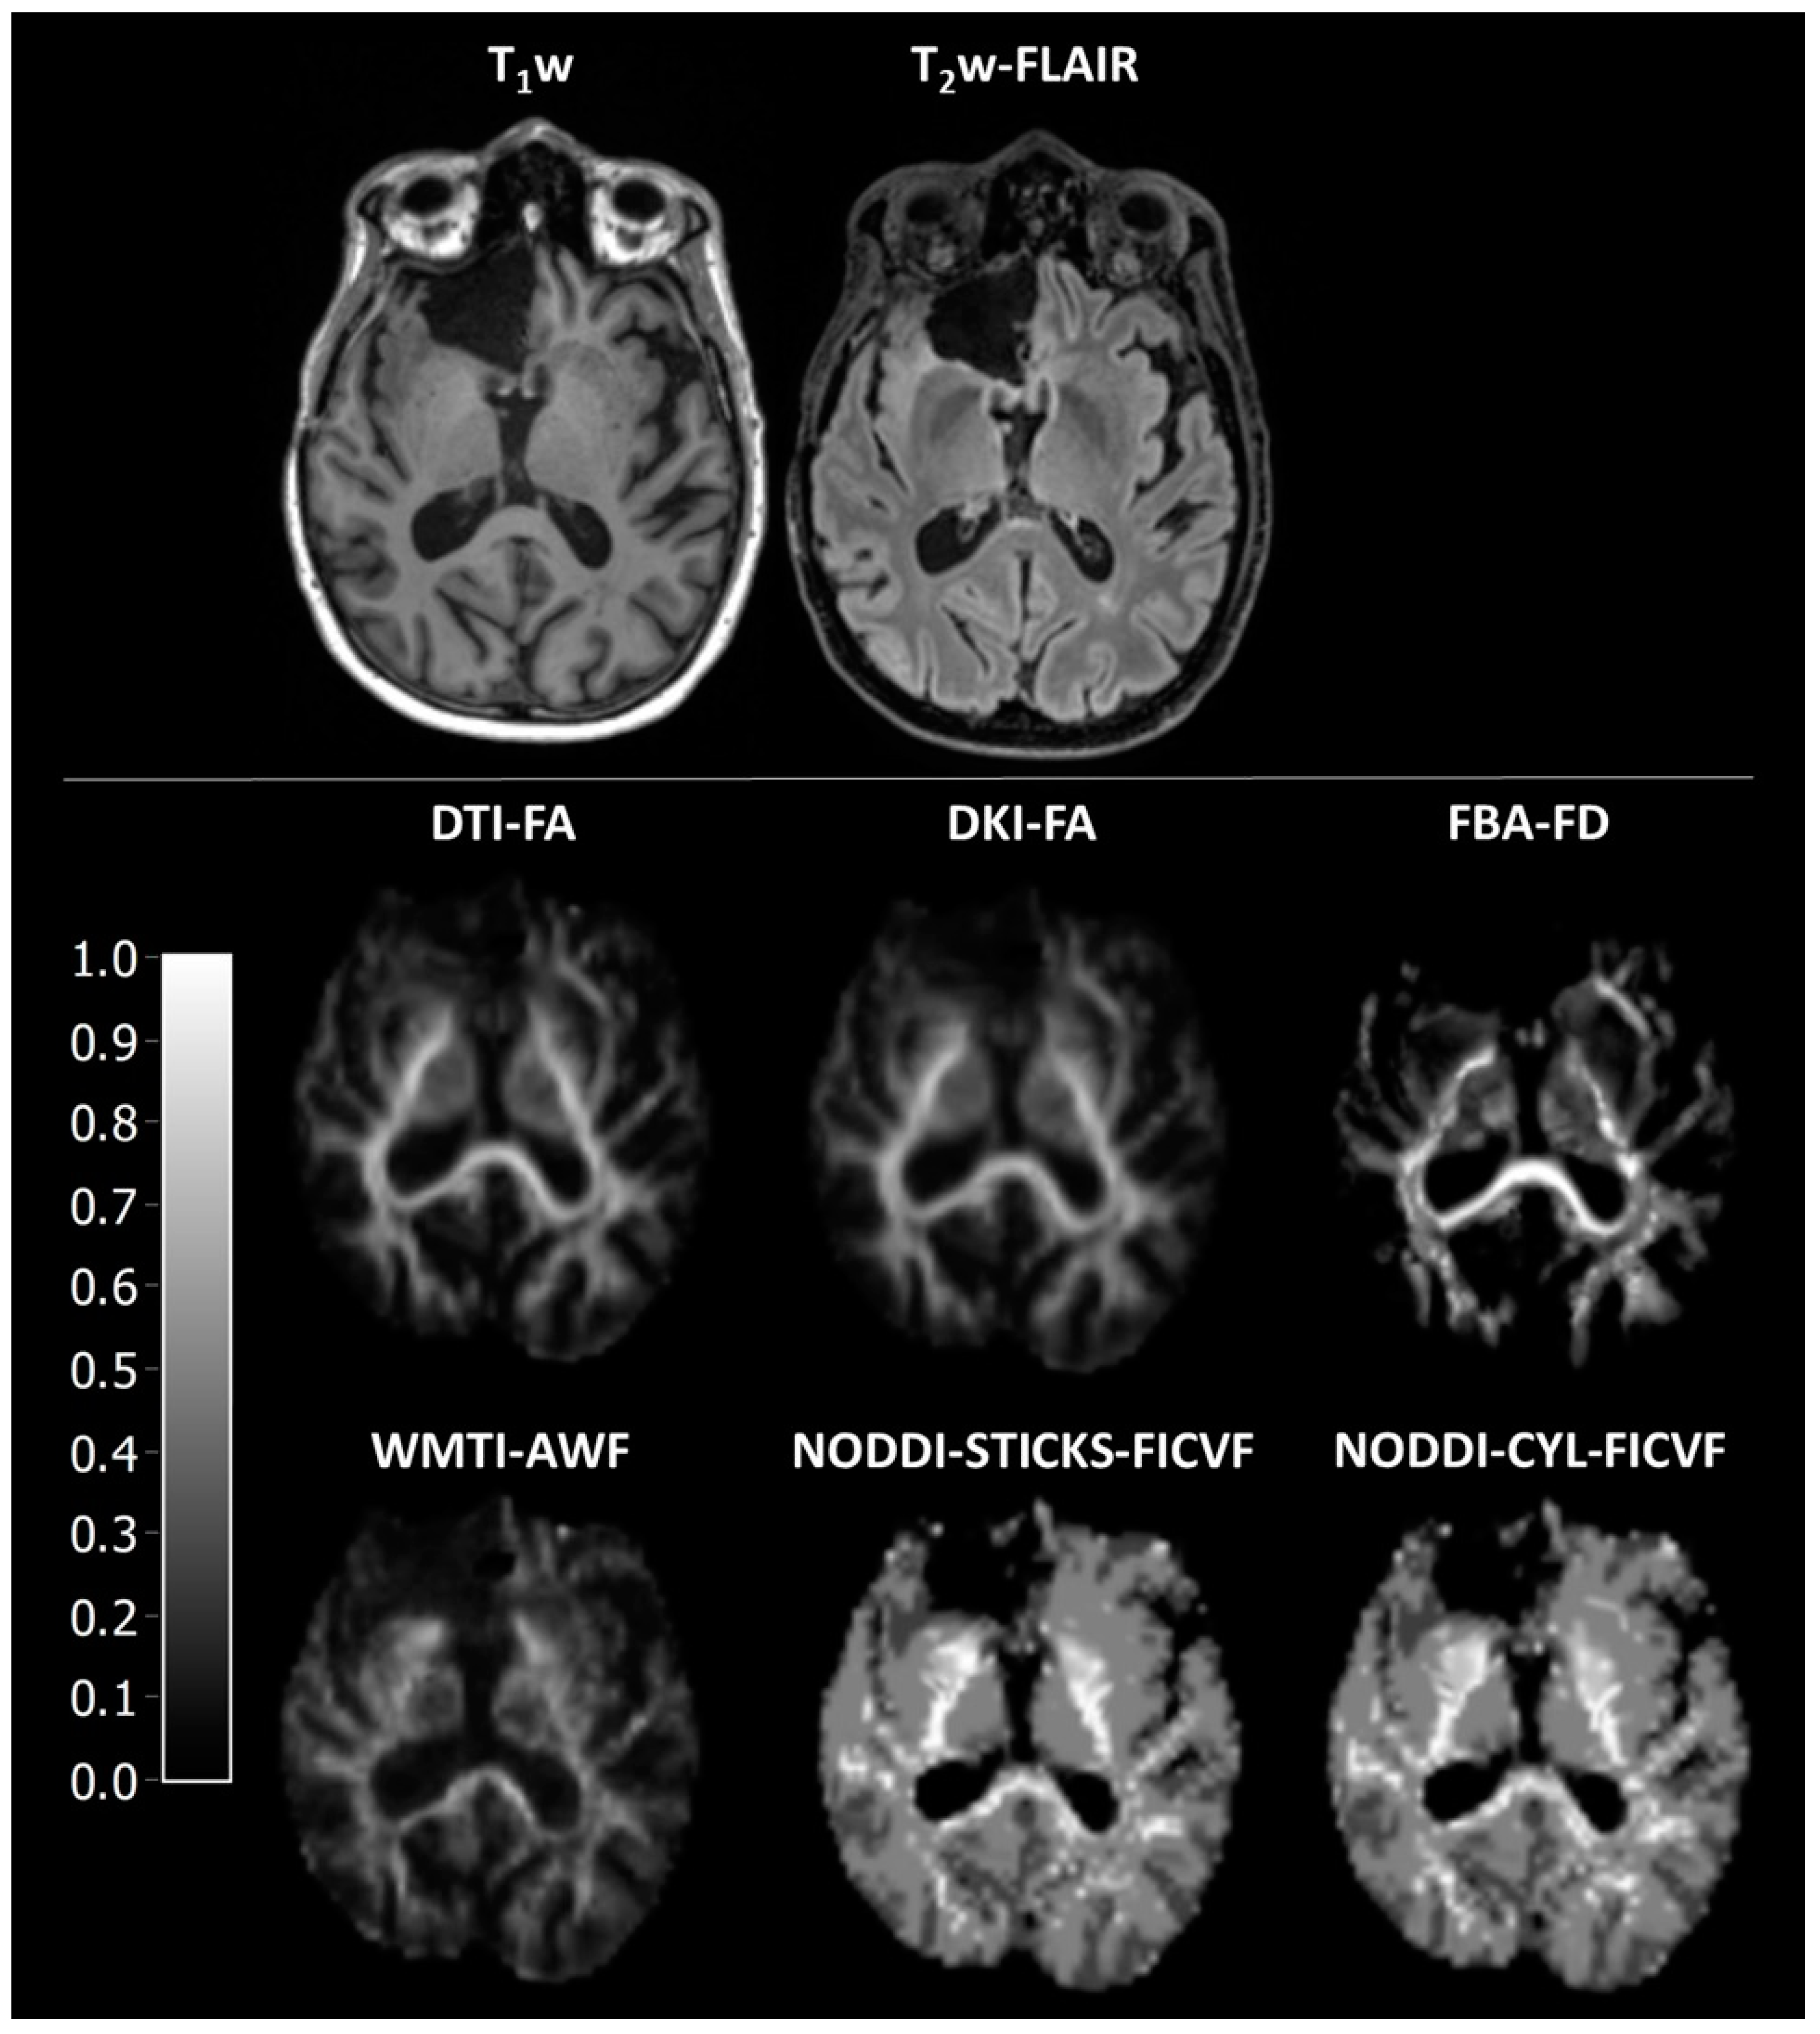

Figure 4. Representative images of mean diffusivity-related parameters. DTI-MD is the mean diffusivity as estimated using diffusion tensor imaging, DKI-MD is the mean diffusivity as estimated using diffusion kurtosis imaging, WMTI-EAS-MD is the extra-axonal space mean diffusivity as estimated using white matter tract integrity, ADC is the apparent diffusion coefficient, NODDI-STICKS-FISO is the isotropic volume fraction as estimated using neurite orientation dispersion and density imaging with the sticks model for neurites, and NODDI-CYL-FISO is the isotropic volume fraction as estimated using neurite orientation dispersion and density imaging with the cylinder model for neurites.

3.5. Assessment of Mean Diffusivity-Related Parameters

Similarly, as expected, all parameters of the mean diffusivity were significantly different between different tissues (H = 34.9–42.9, p > 0.001, Figure 2D and Figure 4, Supplementary Table S1), with a high gradient in the surgical cavity, a lower one in the peri-surgical cavity, and the lowest one in NAWM and WM (Supplementary Tables S2 and S13).

All methods strongly correlated with each other (r = 0.61–0.99, Figure 3D, Supplementary Table S14). Furthermore, a low bias was observed, as depicted by differences in slope and ICC (Figure 3D and Supplementary Table S15) between DTI-MD, DKI-MD, and WMTI-EAS-MD, and between ADC, NODDI-STICKS-FISO, and NODDI-CYL-FISO, but a high bias between the two groups was noticed. When compared to each other, all methods were significantly different to each other (H = 9506, p > 0.001, Table 3, Supplementary Table S6), except for NODDI-CYL-FISO from NODDI-STICKS-FISO (H = −14, p = 1.000). Both DKI-MD and WMTI-EAS-MD have higher values than DTI-MD, whereas DKI-MD seems to have higher estimates than WMTI-EAS-MD for high MD estimates and lower estimates than WMTI-EAS-MD for low MD estimates. Furthermore, both NODDI-CYL-FISO and NODDI-STICKS-FISO have lower MD values than either DTI-MD, DKI-MD, or WMTI-EAS-MD. These findings suggest that while the absolute values were statistically different from each other, the relative change in parameters between the different ROIs was similar for all MD-related parameters.